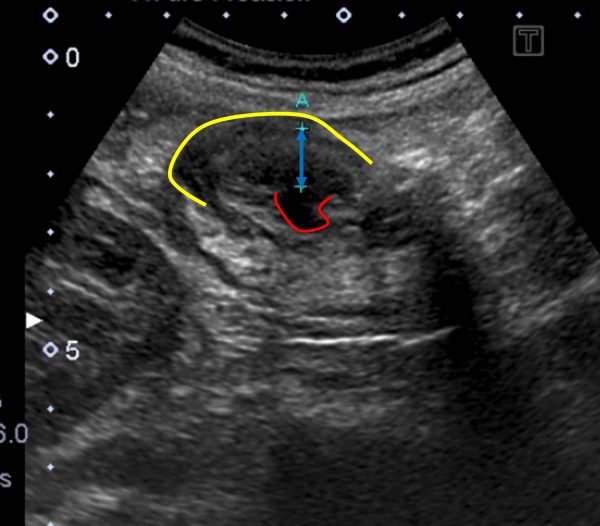

腹部エコー

・横行結腸(黄色部分)に憩室を認め(赤色部分)、炎症により周囲の大腸壁が10㎜大に浮腫んでいました(矢印部分)。

➡検査結果から横行結腸の大腸憩室炎と診断しました。